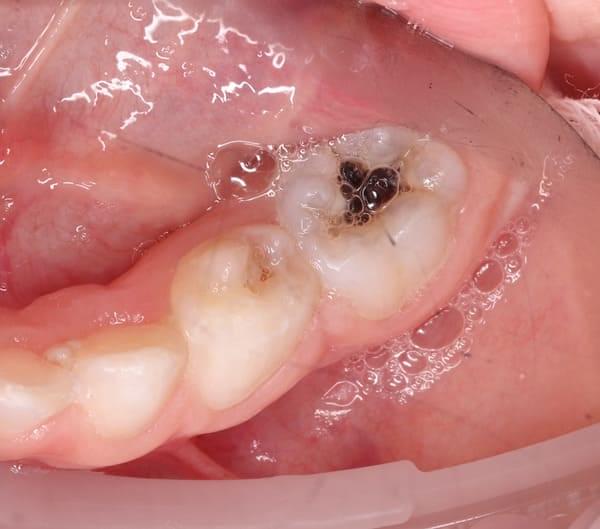

Пульпа (або, як іноді кажуть “нерв”) молочного зуба — це унікальна жива тканина з високим потенціалом до відновлення. Якщо лікар володіє сучасними методиками, він може не видаляти її, а зберегти. Це дуже важливо, адже збережена пульпа забезпечує кращий прогноз для зуба. Якщо ж запалення необоротне, ми проводимо ефективне та безпечне лікування кореневих каналів.

Система кореневих каналів молочних зубів часто складніша, ніж у постійних. Тому ми використовуємо ізоляцію робочого поля за допомогою кофердаму та спеціальне обладнання, щоб гарантувати високу якість лікування.

Важливо розуміти: це не швидка процедура. Вона вимагає ретельного очищення, промивання та пломбування каналів спеціальними матеріалами. Поспіх у цій справі може призвести до серйозних ускладнень у майбутньому.